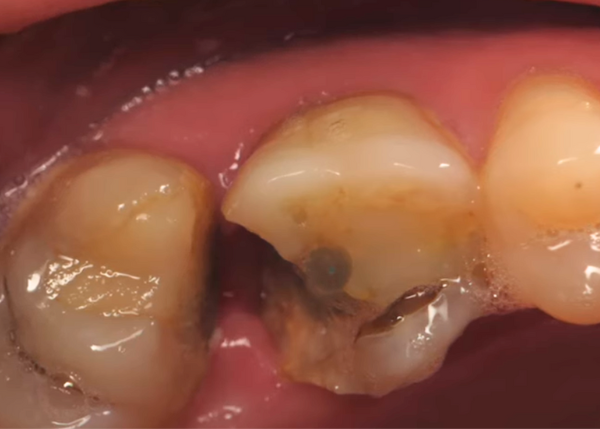

Recurrent caries under crown - "Thinking outside of the box" by Dr. Ahmad Fayad

Introduction: This case was completed by Dr. Ahmad Fayad of Lessard Dental located in Alberta, Canada. Food impaction area that caused massive carious lesion at the distal of the lower... Read More